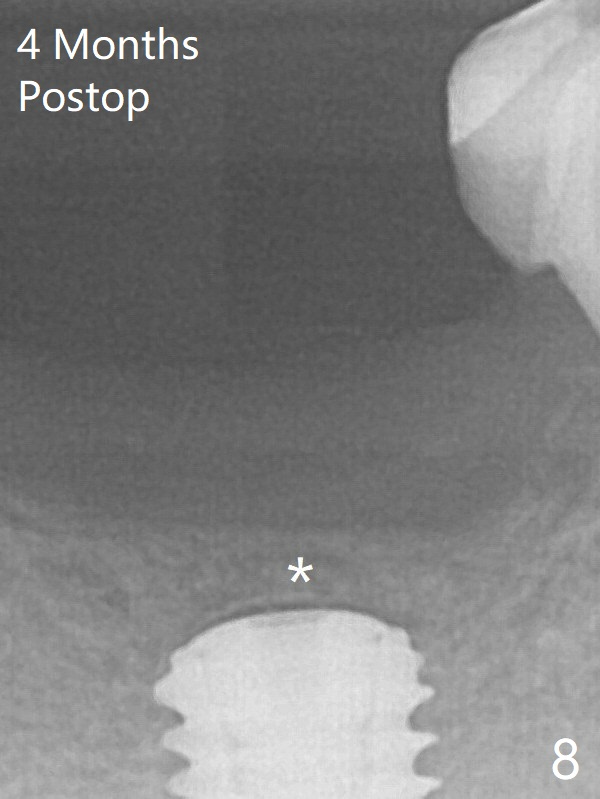

Note radiolucency around the implant (5x11.5 mm) before GBR (Fig.6). There is bone formation coronal to the implant 4 months postop (Fig.8 *), which is removed for uncover.